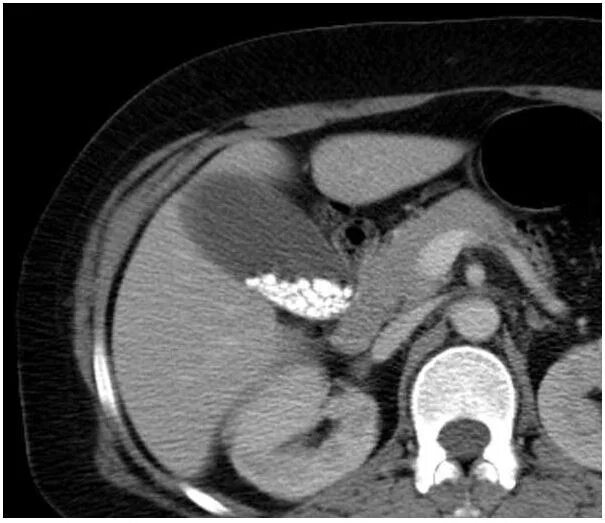

Цирроз печени кт